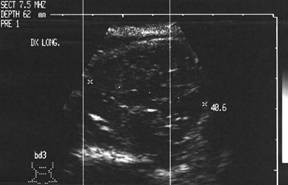

Barbat de 45 ani.

Recidiva linfonodala laterocervicala dreapta dupa tiroidectomie in urma cu trei

ani pentru carcinom papilar.